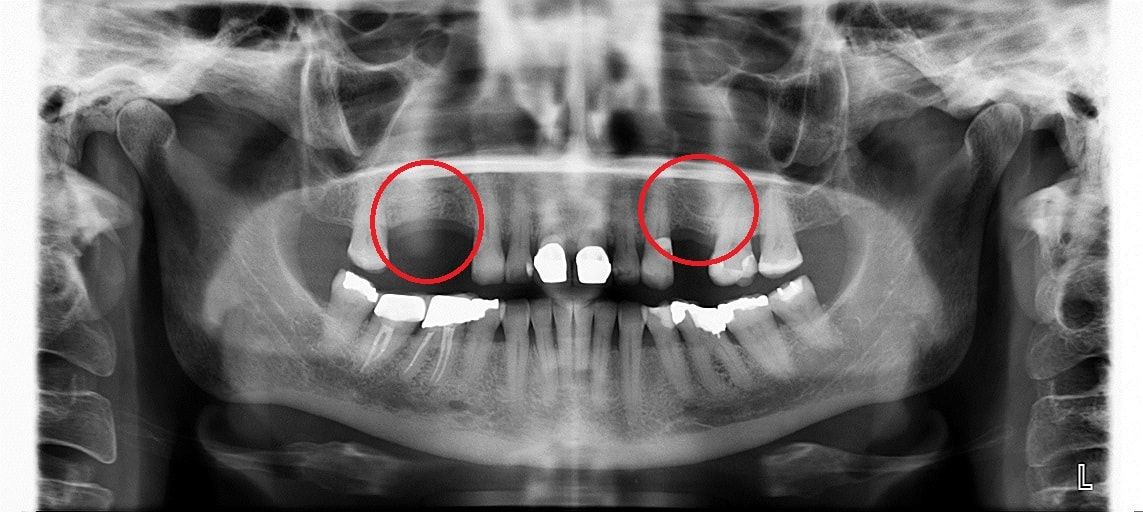

Синус лифтинг

После удаления зуба из-за отсутствия необходимой нагрузки на челюсть, кость в пустующем месте атрофируется. В этом случае перед имплантацией необходимо восполнить объем костной ткани.

Разновидность костной пластики направленной на увеличение объема костной ткани верхней челюсти в районе гайморовых пазух.

Открытый синус лифтинг

Открытый синус-лифтинг применяется, когда для установки имплантата не хватает более 3 мм костной ткани. При проведении этой операции имплантация в ряде случаев возможна только после полного восстановления кости челюсти.

Закрытый синус лифтинг

Закрытый синус-лифтинг подходит для наращивания небольшого объема костной ткани (1-3 мм). Он менее травматичен, чем открытый. Подсадка костного материала проводится через небольшое отверстие для имплантата.

При закрытом типе синус-лифтинга имплантация проводится сразу. Вам не придётся лишний раз посещать стоматолога.

• до синус-лифтинга

• после синус-лифтинга

• после установки имплантатов в верхнюю челюсть

• коронки установленные на имплантаты